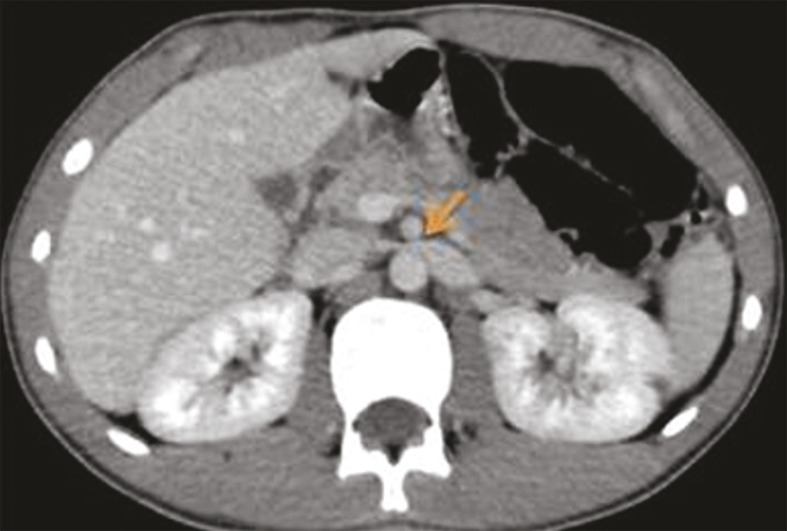

La tomodensitométrie (TDM) a montré une dilatation de la veine rénale de 9 mm, en amont de la pince aortomésentérique (fig. 1) et un matériel hypodense au niveau de la veine spermatique homolatérale, en rapport avec un thrombus (fig. 2).

La tomodensitométrie (TDM) avec injection de produit de contraste objective cette compression de la veine rénale gauche dans la fourchette aortomésentérique, l’angulation entre l’aorte et l’artère mésentérique supérieure (supérieure à 41 °), la distension des veines gonadiques et la congestion pelvienne.2